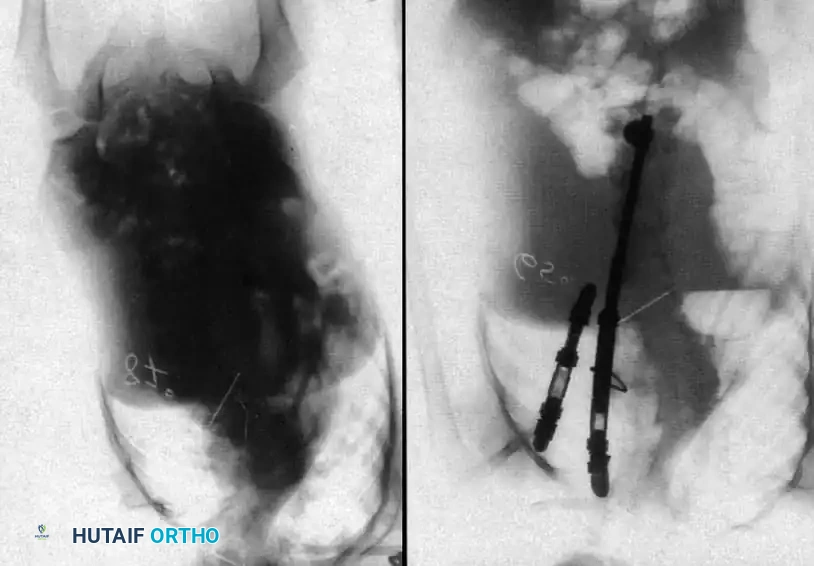

Image

Radiographic examples of progressive congenital curves requiring early intervention.